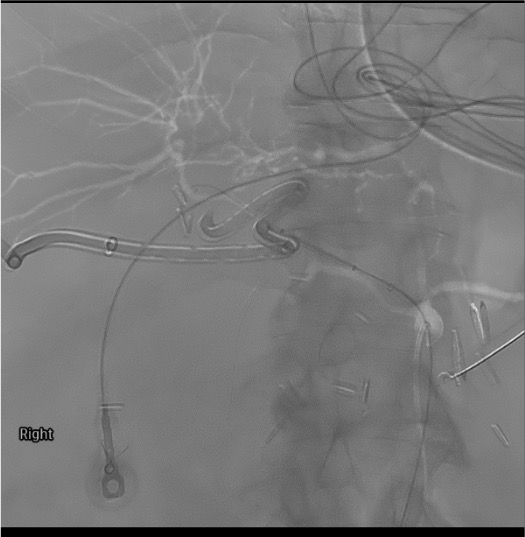

- Covered stent principle: Stent is placed in CHA spanning the GDA stump origin, maintaining hepatic perfusion while excluding the bleeding stump. Hepatic flow is preserved — liver does not lose its blood supply.

Covered stent deployment

Completion angiogram

Covered stent thrombosis on follow-up CT

Likely cause: Very common (~50% long-term) — stent in an infected field with sluggish hepatic flow or suboptimal stent sizing.

Next step: Do NOT panic. Hepatic collaterals typically develop after Whipple, making stent thrombosis usually asymptomatic. Treat only if symptomatic (rising LFTs, hepatic infarcts). Expectant management in most cases. Anticoagulation in selected symptomatic cases.